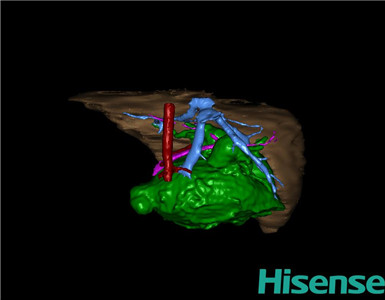

术前三维重建:

重建图片

通过调节窗宽窗位调整CT序号,对肝实质,胆囊,下腔静脉,肿瘤,肝动脉、门静脉及肝静脉等进行三维重建;系统自动计算肝脏体积。

术前手术方案的规划。